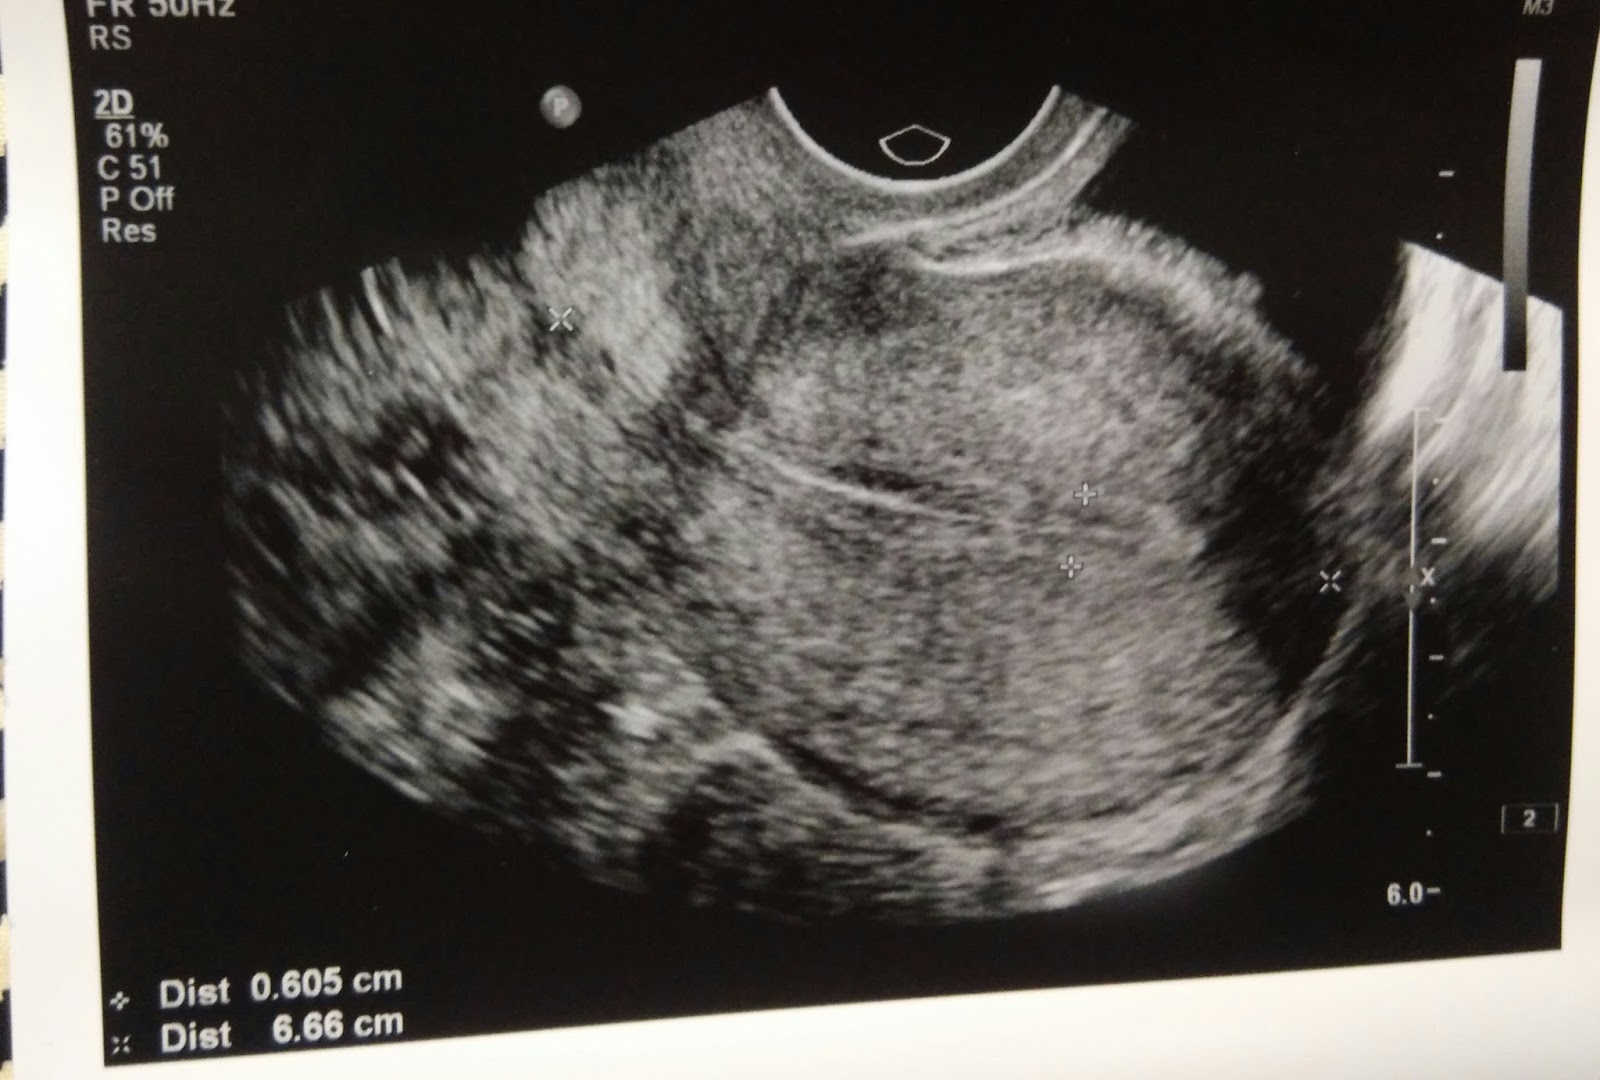

日記8月7日,星期五,經期後的第八天。

經過上月內膜過厚的教訓,所以今次提早抽血及照內膜,

而今日提早照完後,下星期要再多照一次,

希望一切順利吧。

不過感覺今次是放鬆了很多,始終有了上次經驗,

我得到的教訓是不夠厚,可多等幾天,

但過厚就一定不可去,所以一切也放軟手腳了。

今次見醫生沒有什麼壓力,因才剛剛完經,

應該內膜也不會有太大問題的。

醫生看後也表示一切正常,

內膜厚度也有約6mm,

希望之後一直加厚,但又不要過厚吧。

而驗血報告明早會收到。

下星期三再覆一次診,到時候便知道能否去放胎。